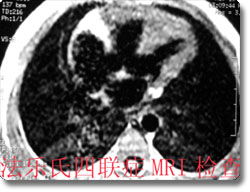

本科室有丰富的先天性心脏病的诊断经验和手段,通过心血管造影、MRI等方法,可以对先天性心脏病法乐氏四联症、三联症、三尖瓣异常、动脉导管未闭、房(室)间隔缺损、大血管位置及引流异常等在术前作出比较准确的影像诊断和评估,为临床手术治疗提供可靠的诊断依据,极大的提高了先天性心脏病的诊治水平,对间隔缺损和动脉导管未闭患者还可进行介入性微创治疗,在国内处于领先地位。 |